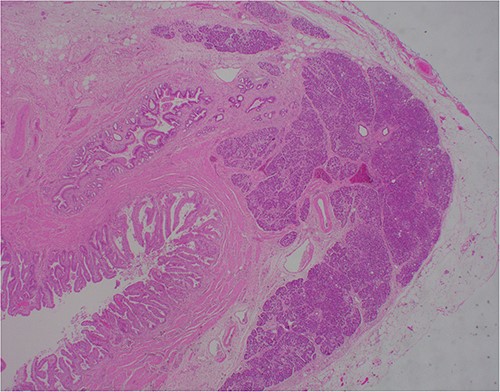

At outpatient phone clinic review 2 months post-surgery, the patient had recovered well, and his pre-operative symptoms of nausea, vomiting and pain had completely resolved. The histopathology of the gallbladder found chronic cholecystitis with cholelithiasis, in addition to a 6 mm focus of pancreatic heterotopia in the gallbladder wall. This heterotopic tissue contained acini, ducts and islet cells, classifying it as Type I pancreatic heterotopia (Figs 1–3).

×2 objective lens; low-magnification photograph showing an area of pancreatic heterotopia.